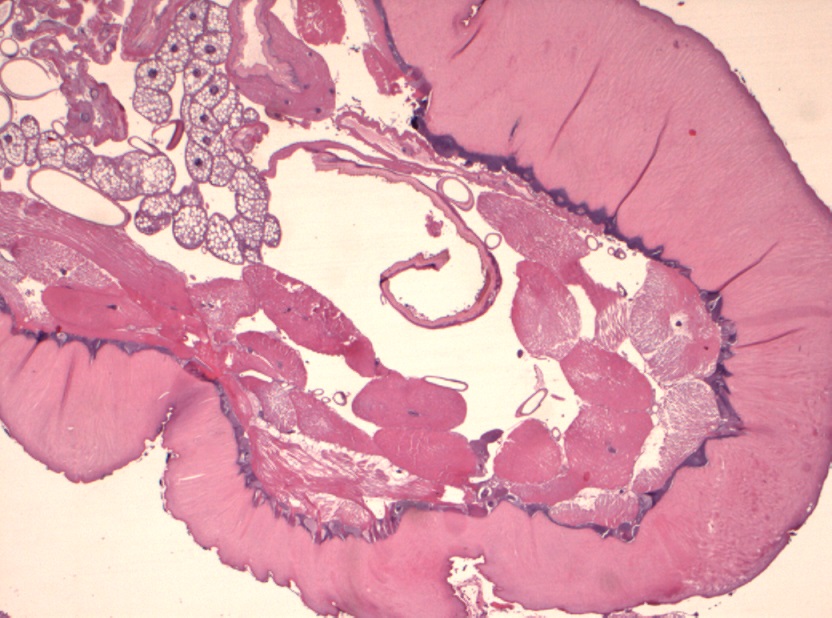

Foto microscopiche: purtroppo non ho potuto fare foto "panoramica"; ho fatto alcune foto al minore ingrandimento; si possono osservare le componenti della larva caratterizzata da spessa cuticola con sparse "spine" in superficie, che penso che siano i rostri; internamente alla cuticola si osserva strato di tessuto muscolare liscio ed organi interni conservati; ho fatto anche una foto del lembo di cute e sottocute sovrastante centrato da tragitto fistoloso circondato da denso infiltrato infiammatorio costituito da linfociti, plasmacellule, istiociti e più rari granulociti eosinofili.

Io vi metto due foto macroscopiche e quelle istologiche, che in pratica rappresentano le "fette" della larva partendo da un'estremità (bocca?), poi il centro (forse l'apparato digerente?) e l'altra estremità...spero siano sufficienti :)

It is the larvae of subcutaneous warble fly (Hypodermatinae).

The characteristic feature from larvae sclerosed presence of strong hooks arranged in a ring.